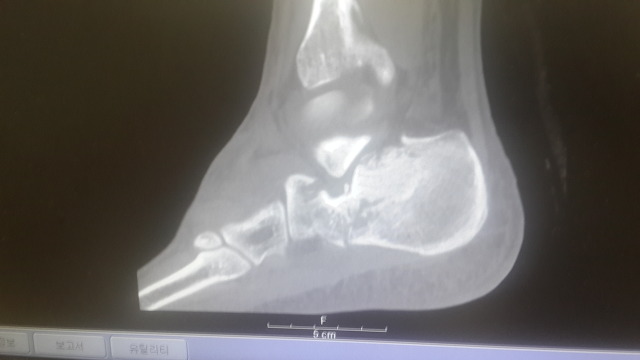

아래는 수술 전 찍은CT 와 X-ray 사진들입니다.

종골이 으스러졌다고 하시더라고요.